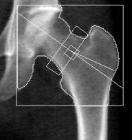

大腿骨の測定